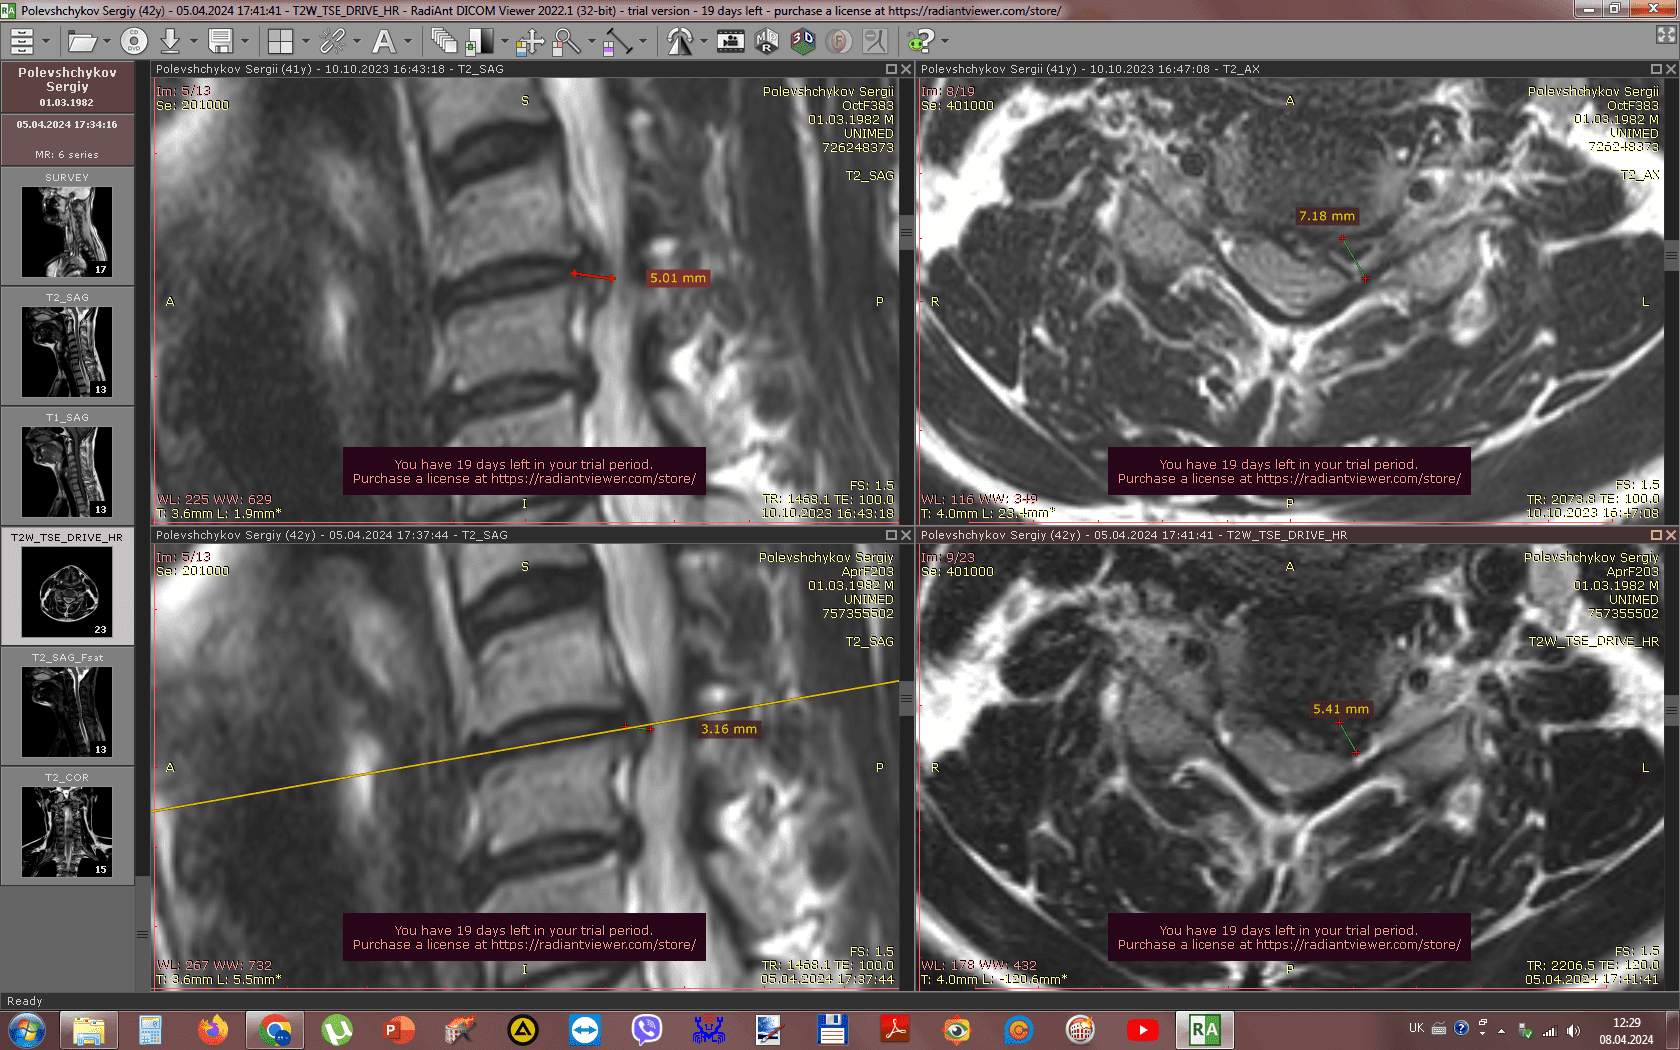

Метод лікування грижі шляхом стимуляції резорбції в Україні був впроваджений у 2020-2021 роках.  Алгоритм оцінки грижі на предмет резорбції, що використовується у клініках – є авторським, розроблений лікарем Боханом А.Ю.